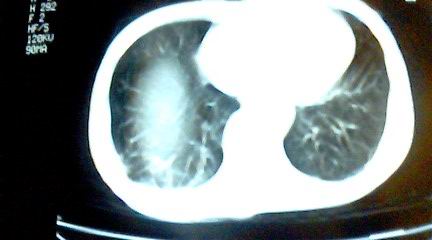

标题: CT25218:请教!胸部CT,胸8椎体骨质破坏,伴周围软组织肿。 [打印本页]

标题: CT25218:请教!胸部CT,胸8椎体骨质破坏,伴周围软组织肿。

患者,女41岁,肢体乏力。

双肺及胸椎结核。

双肺及胸椎结核。支持!

两肺上叶继发性肺结核;胸椎结核并椎旁寒性脓肿形成。

两肺上叶继发性肺结核;胸椎结核并椎旁寒性脓肿形成